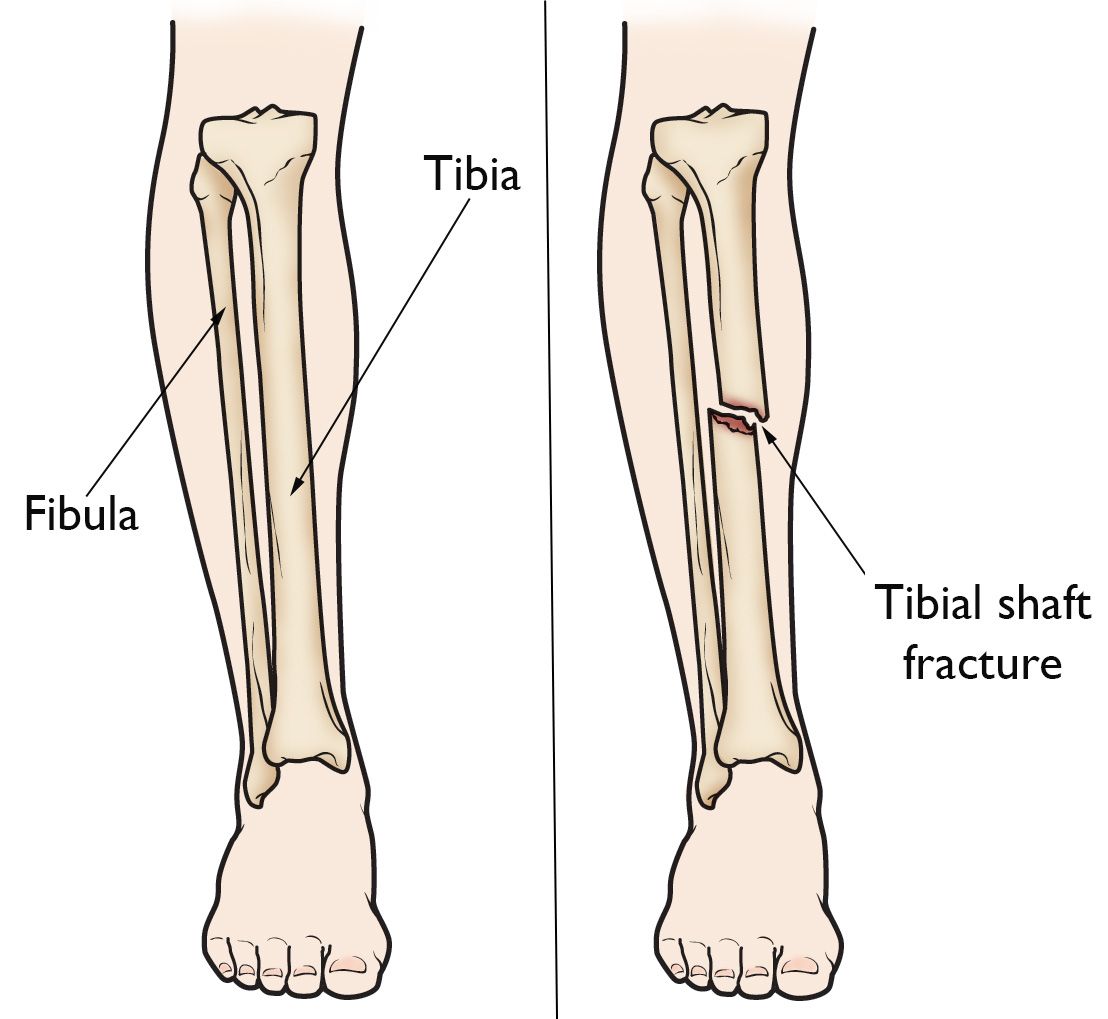

با اعلام باشگاه منچسترسیتی، یوشکو گواردیول دچار شکستگی استخوان درشتنی (تیبیا) پای راست شده است. طبق اطلاعیه سیتیزنها، گواردیول اواخر همین هفته تحت عمل جراحی قرار خواهد گرفت. در حال حاضر روند بررسیهای پزشکی ادامه دارد تا میزان دقیق مصدومیت و دوری مدافع کروات از میادین مشخص شود. در ادامه مشکلات دفاعی منچسترسیتی، این باشگاه روز دوشنبه و ساعاتی پیش از اعلام جزئیات مصدومیتها، مکس الین مدافع میانی ۲۰ ساله خود را از دوره قرضی یکفصلهاش در واتفورد فراخواند. این در حالی است که جان استونز از اوایل ماه دسامبر به دلیل مصدومیت عضله ران در دسترس نیست و ناتان آکه هم پس از عمل جراحی پا در فصل گذشته، تنها بهصورت محدود مورد استفاده قرار گرفته و در فصل جاری لیگ برتر فقط دو بار در ترکیب اصلی گواردیولا به میدان رفته است.

مطابق ارزیابی پزشکان، دوره درمان شکستگی استخوان تیبیا 4 تا ۶ ماه تخمین زده میشود. بازگشت این مدافع کلیدی در فصل جاری، به روند درمان و همچنین ریسک پپ گواردیولا روی وضعیت فیزیکی بازیکن خود بستگی خواهد داشت.